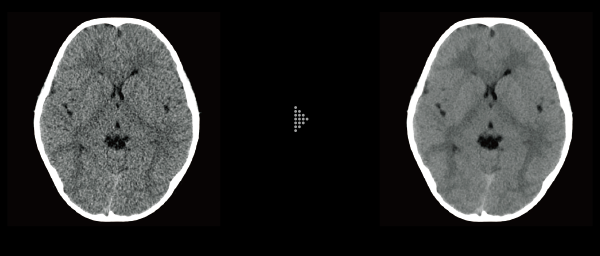

FBP(Left)

Intelli IPV(Right)